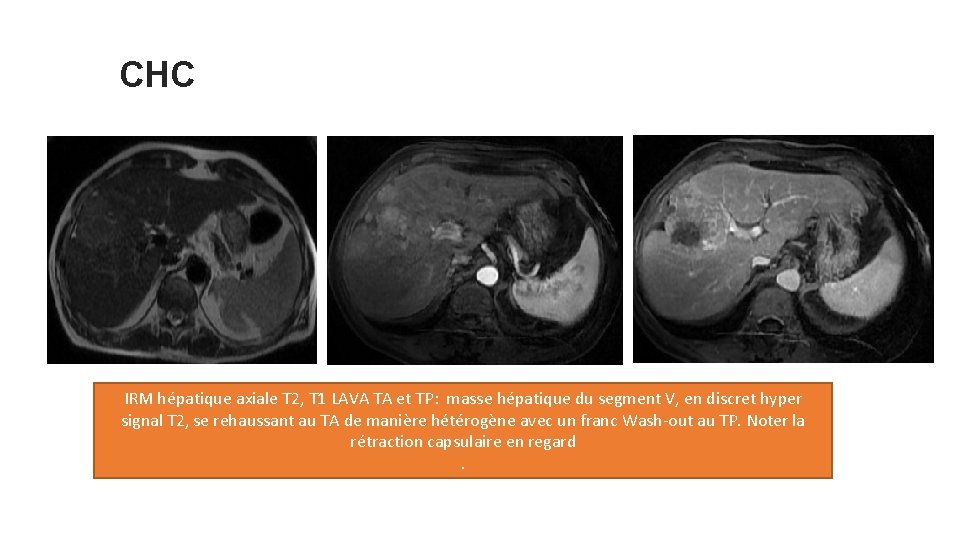

CHC IRM hépatique axiale T 2, T 1 LAVA TA et TP: masse hépatique du segment V, en discret hyper signal T 2, se rehaussant au TA de manière hétérogène avec un franc Wash-out au TP. Noter la rétraction capsulaire en regard.